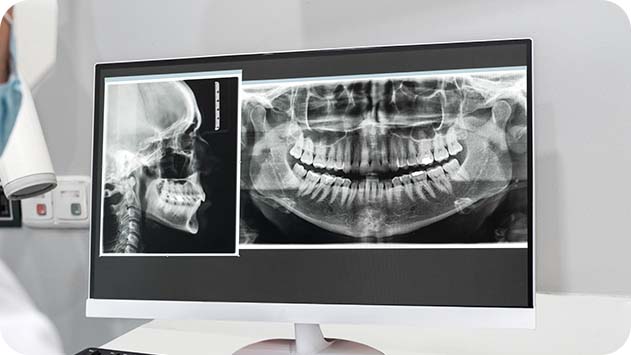

리페이스치과병원은 3D CT 재구성

시뮬레이션 기술을 활용해

과거 수술 데이터와 현재 구조를 비교 분석하여

개인별 최적 전략을 수립합니다.

과거 수술 데이터 vs 현재 상태

오버레이 비교

3D CT 분석 및 정밀 진단으로

기존 수술의 실패 원인 파악

교합·호흡·저작 기능 회복을 위한

360도 시뮬레이션